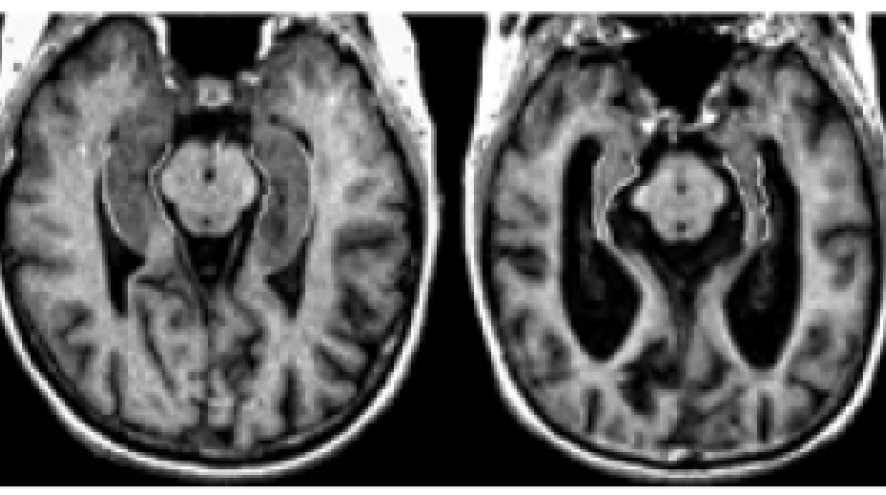

Two MRIs that depict the brain of a person without Alzheimer's, and a person with Alzheimer's.

MRI images courtesy of Sunnybrook and Women's College Health Sciences Centre.